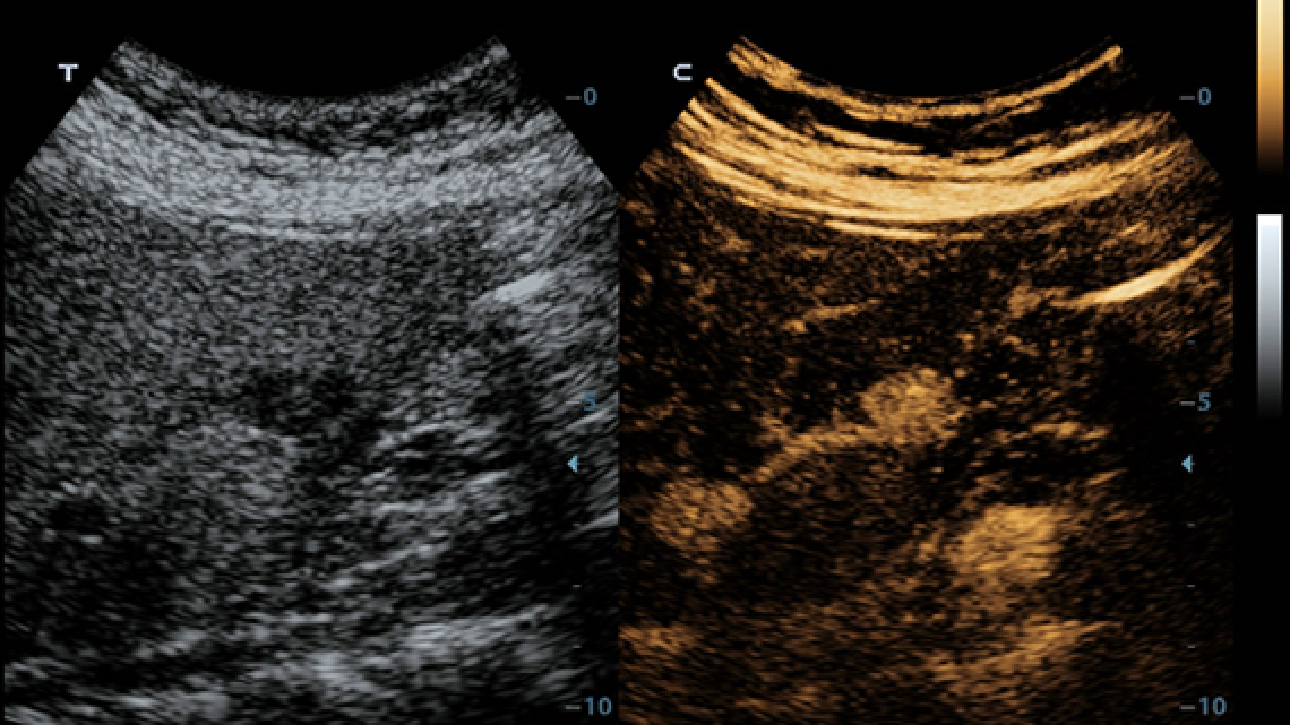

Klinische Bilder

• p22-s9-1

Raumforderung des Bauches

• p22-s9-2

Raumforderung der Blase, 2D

• p22-s9-3

Allgemeine Schlagader IMT

• p22-s9-4

Allgemeine Schlagader PW

• p22-s9-5

Dilation des Milchgangs

• p22-s9-6

Kindy HR Flow

• p22-s9-7

Leber, 2D

• p22-s9-8

Natural-Touch-Elastographie

• p22-s9-9

Subskapulare Muskelsehne

• p22-s9-10

Raumforderung der Schilddrüse CFM

• p22-s9-11

Schilddrüse, 2D

• p22-s9-12

UWN+(CEUS)